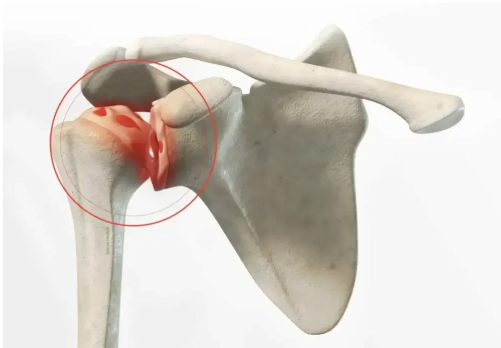

Après un traumatisme, les ligaments peuvent perdre leur fonction stabilisatrice. La chirurgie de l’épaule rétablit la solidité ligamentaire et assure une stabilité durable lors des activités quotidiennes.